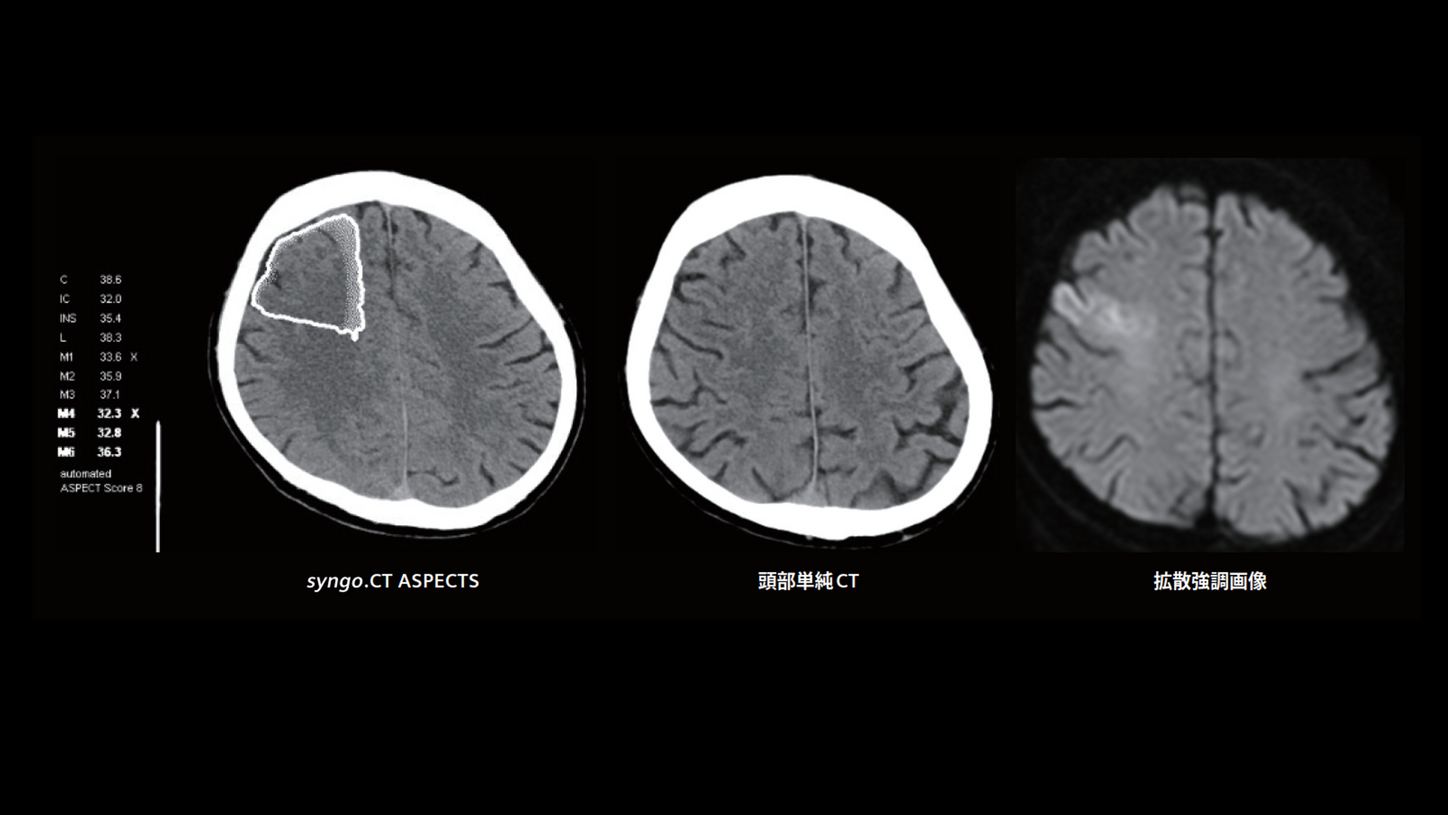

急性期脳梗塞による低吸収域の検出

syngo.CT ASPECTS(早期脳虚血変化の検出)に代表されるアプリケーションは、画像所見の見落としを防ぐための非常に有用な診断支援機能だと感じています。従来の頭部単純CTでは検出しづらかった急性期脳梗塞による低吸収域がsyngo.CT ASPECTSで検出され、同日の頭部MRI 検査の拡散強調画像でも同部位に高信号を示す脳梗塞が確認されました(発症 8:45、病着 9:23、CT 撮影 9:45、ELVO (-))。最終的にMRIで診断するにしても、CTによるsyngo.CT ASPECTSで早期脳虚血変化を検出できれば、重点的にその部分を確認できますので、臨床上とてもありがたいことです。